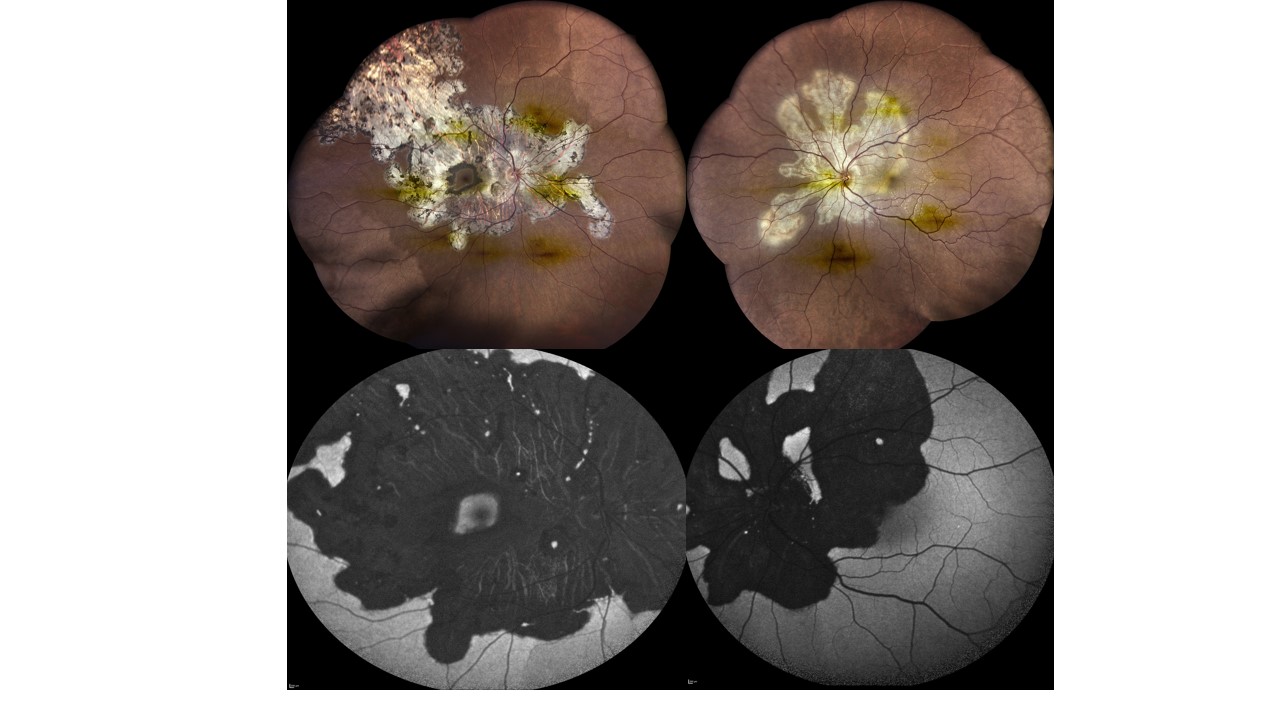

Description: Geographic Helicoid Peripapillary Choroidopathy

A swirling octopus of inflammation unfurled across her fundus— pale, relentless tentacles advancing toward fovea, threatening the heart of sight.

Yet vision did not yield: 6/6 in both eyes.

A 34yr/F presented with active disease in her left eye with fovea partly claimed by the advancing helicoid; the right fovea untouched, as shown in fundus images. After steroids, she was maintained on mycophenolate mofetil.

Eighteen months later, autofluorescence images as shown- revealed the creature subdued, its once-furious glow softened into healed serpiginous scars.

The battle left its marks, but not her vision— a quiet triumph of light over the lurking octopus within.